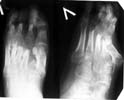

A colleague of mine from another facility presented a case of foot malunion (images attached) among other severe injury sequelae (there is also osteomyelitis of the femur and pelvic nonunion). The injury was 6 months ago. The colleague has some considerations about the other regions.

What about the foot - it is in stiff equinus and there is a pressure sore above the base of the Ist metatarsal bone. What treatment plan for the foot deformation you would choose? Just correct the equinus with external lfixator? Perform osteotomy of metatarsal bones? All or 1st only?

I think definitely a metatarsal osteotomy and a posterior lengthening and capsular release which could be done open or by the Ilizarov technique.